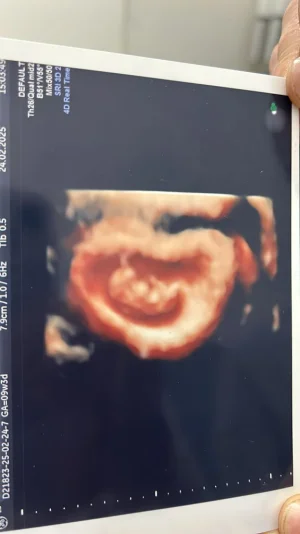

bizde bu gun 9 haftalık olduk

sadece kesem ilk ultrasonda fasuyle gibiydi. Ona erkek diyorlar ama herkeste aynımı bilemem